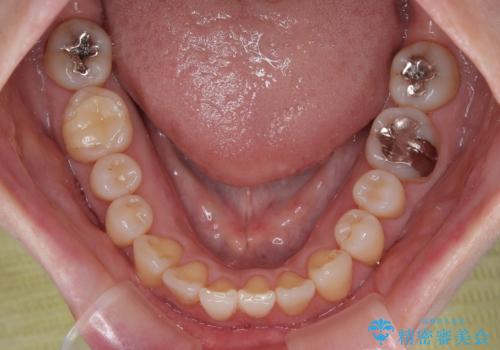

前歯のデコボコをインビザライン・モデレートで矯正治療

- 上下前歯のデコボコを気にして来院された患者様です。

安価なインビザラインパッケージを用いての治療を希望されており、デコボコの程度が中等度であったため、インビザライン・モデレートを用いて矯正治療を行うこととしました。

インビザライン・モデレートは、製作できるアライナーの枚数に制限があるため、移動可能な量に限りがあるものの、インビザライン・ライトよりも枚数が多いため、幅広い症例に対応可能です。